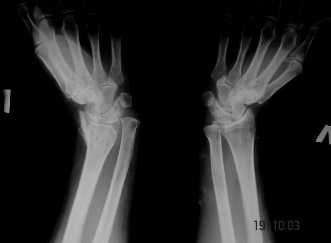

Уважаемые коллеги! Обратилась женщина, 55 лет. Травма 3 месяца назад, лечилась по месту жительства (Рис.1). Косорукость, боли, ограничение движений.

Досняли - рис.2-6. Хотелось-бы услышать мнения об объеме операции. С уважением, Юрий Алексеевич Булахтинглавный травматолог Камчатского Военно-морского госпиталя

u pazientki po nauchnomu ulna abutment/impingment syndrome posle posttraumaticheskogo ukorochenia radiusa

na rengene znachitelnoe ukorochenie radiusa, sustavnaia poverchnost naklonena dorsalno chresmerno , chetko vidno nekongruentnost DRUJ - distalnogo radioulnarnogo sustava ,ulna prosto vtikaetsia v triquetrum .

Да, действительно, в наличии так называемый посттравматический ulnar impaction syndrome. Есть несколько вариантов лечения этой патологии-данного случая. Вполне можно выбрать вариант и предложенной выше тактики. А кто-то даже после остеотомии лучевой кости наложит аппарат внешней фиксации и одновременно устранит дорсальную ангуляцию и удлинит лучевую кость. Можно предусмотреть и другие варианты. Если не очень расстраивает дорсальная ангуляция, то при отсутствии артроза в области дистального радиоульнарного сочленения ( а пока такого, по-видимому, нет)и нестабильности этого сустава можно просто укоротить локтевую кость. Причем возможно сделать поперечную остеотомию ( если есть ладонный или тыльный подвывих головки локтевой кости, то можно сделать еще и клиновидную остеотомию по ладони или по тылу), либо выполнить косую остеотомию ( при подвывихе головки даже клин в этом случае не надо делать). Если есть артроз, нестабильность, то нужно рассматривать другие варианты - Дарраха в модификациях, Сауве-Капанджи, артропластику(?).